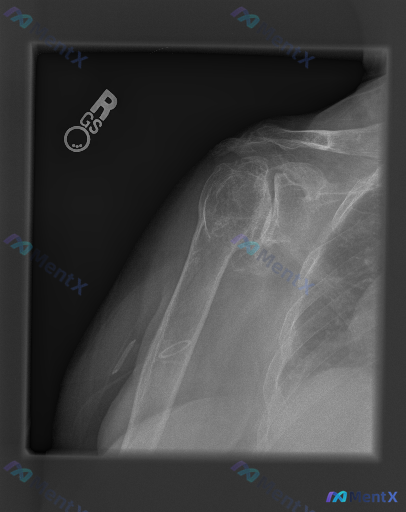

整理到一张右肩正位X光片的影像资料,先抛出来大家一起看思路。 基础影像表现: - 肱骨近端有金属内固定影(推测髓内钉) - 肱骨近端可见明显骨质破坏、结构紊乱,多发骨折线累及肱骨头及大、小结节,呈粉碎性改变 - 盂肱关节间隙变窄、关节面粗糙,关节盂缘有骨赘;肩锁关节也有退变、骨赘 - 肱骨头密度不均...